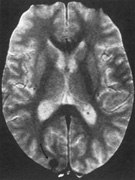

Fig. 18. Magnetic resonance imaging scan of patient with stroke causing a right hemiachromatopsia as well as partial superior quadrantanopia.